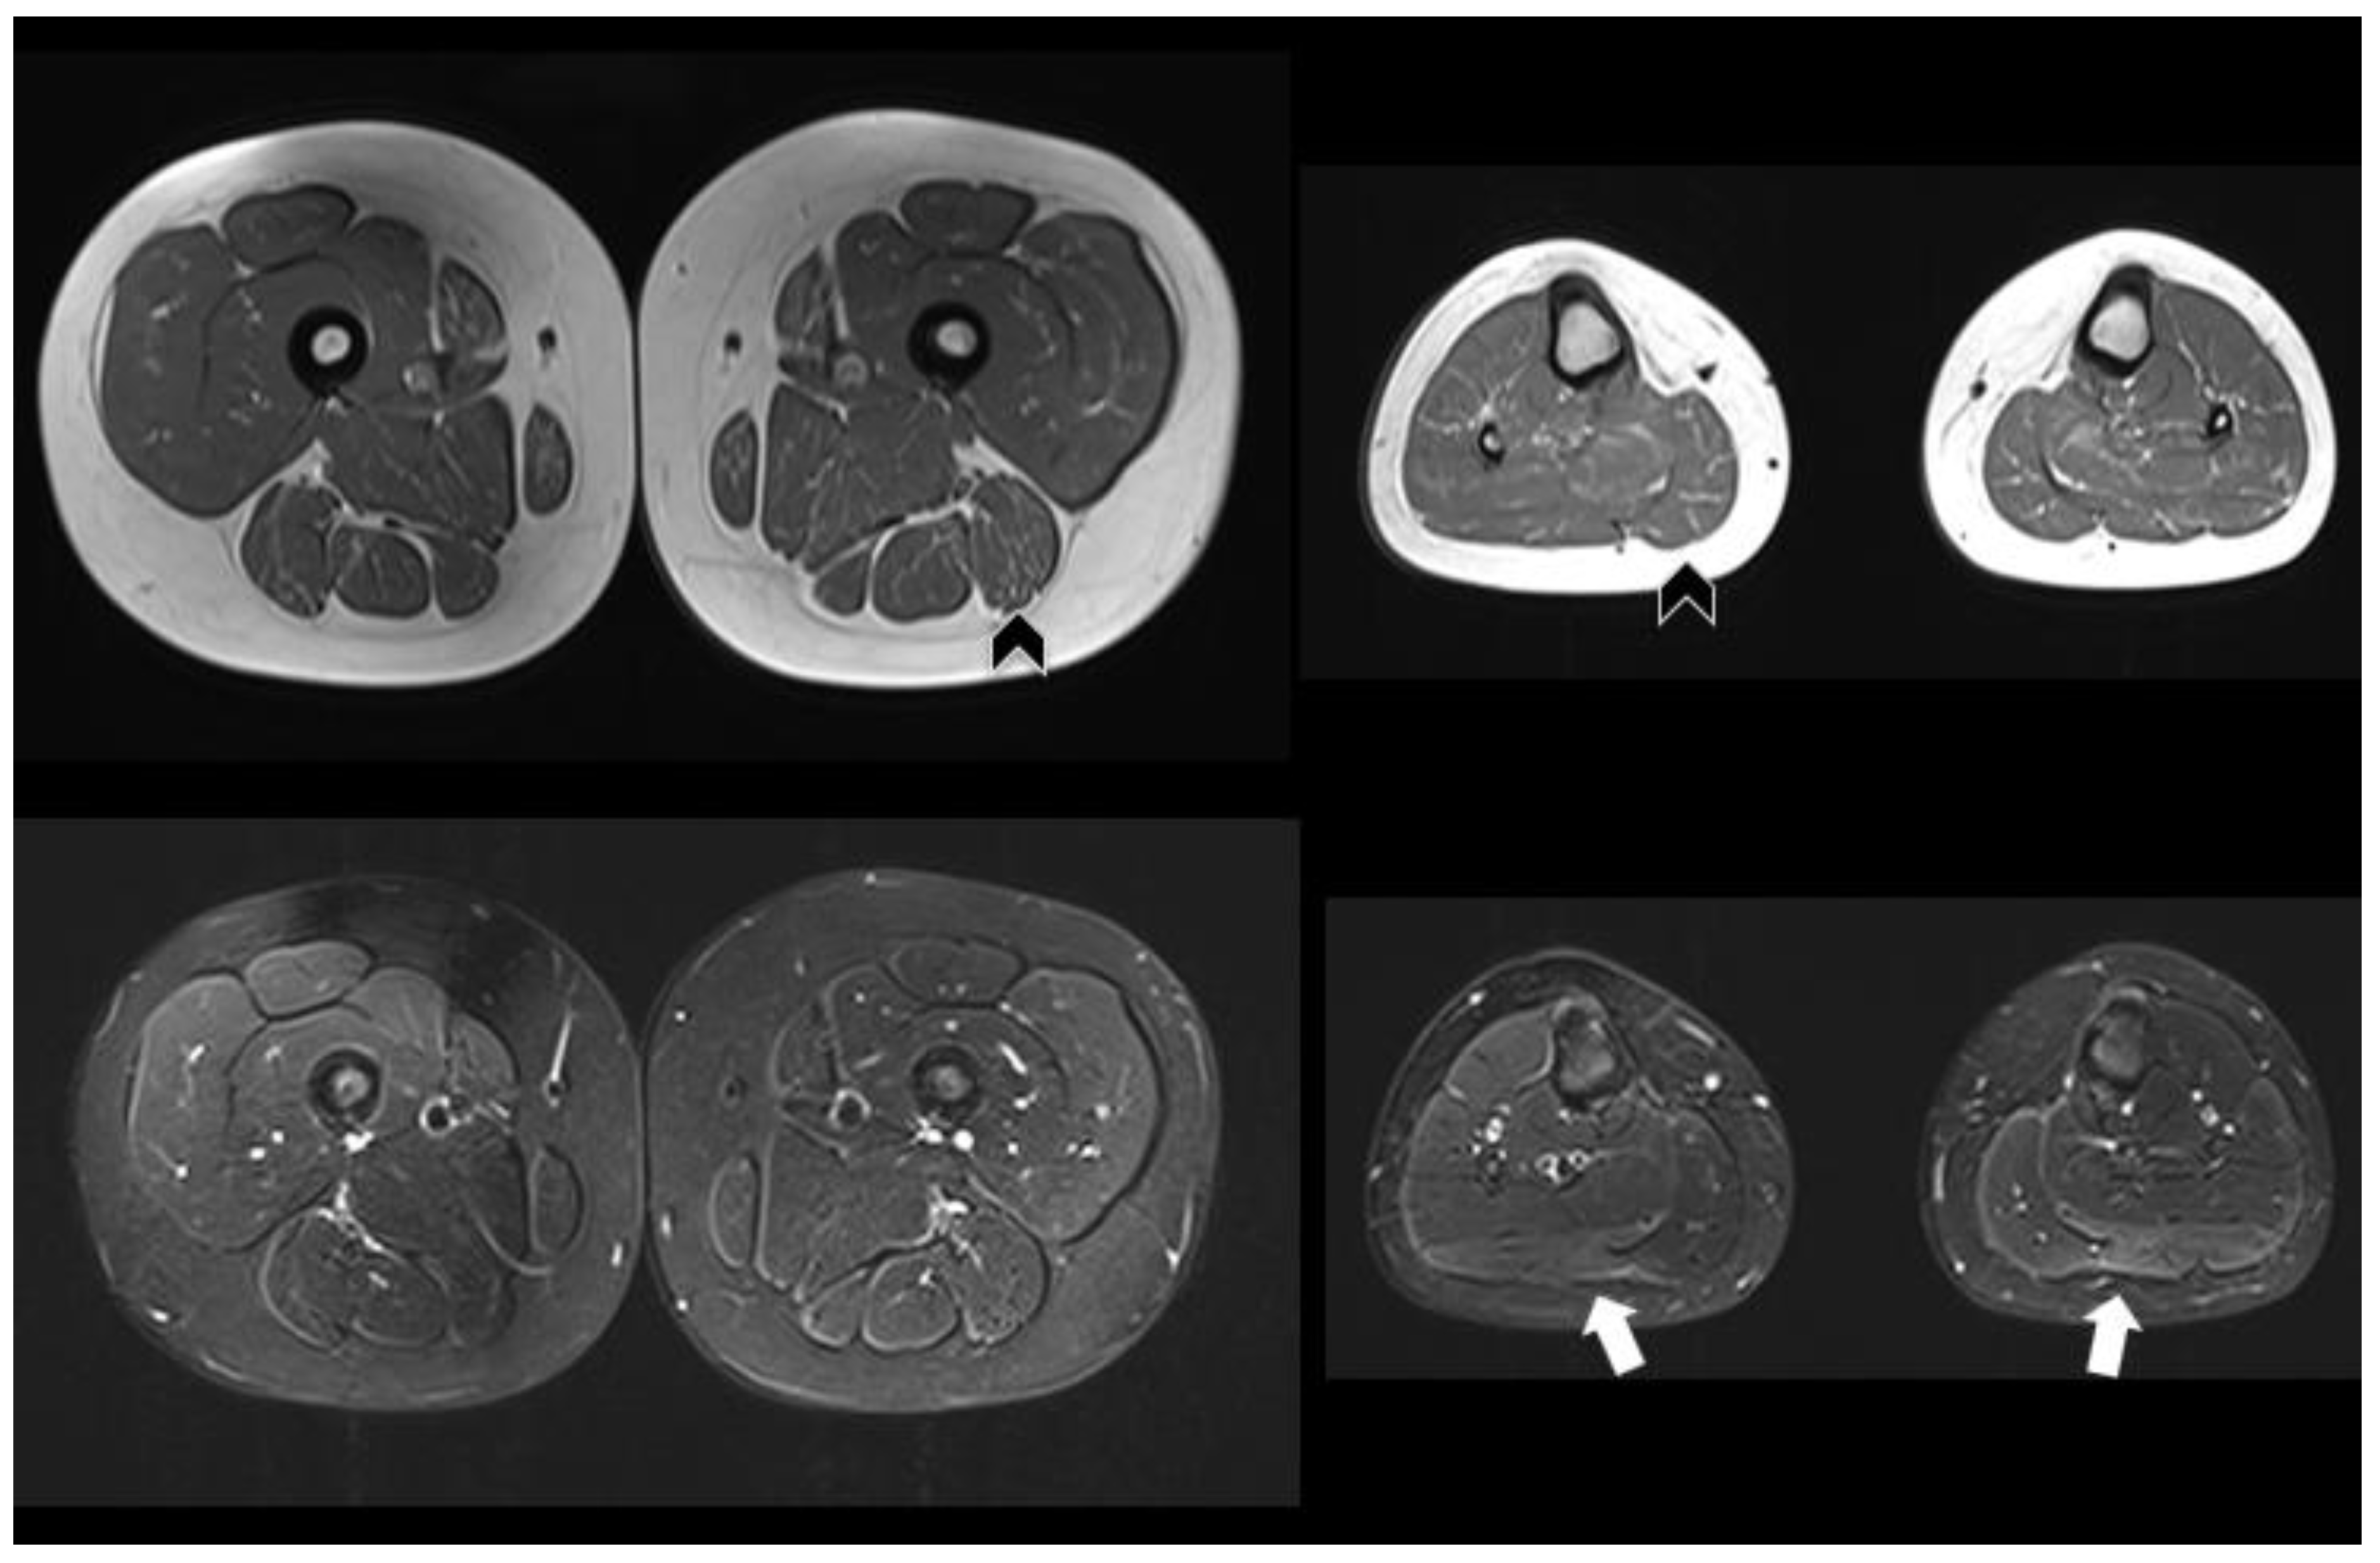

Meanwhile, the patient’s brother and sister underwent extensive testing. No symptoms regarding the 8-year-old sister were reported (patient 2). She was admitted to the pediatric department at 7 years old because of a urinary tract infection, and during an abdomen ultrasound, mild steatosis was reported. As a screening for Pompe disease, she underwent dosing of enzyme activity on dry blood, which resulted in low activity (1.2 µmol/L/h, n.v. > 2), and sequencing of the GAA gene, which found the same mutations as patient 1. A neurologic visit, electromyography, and echocardiography were performed, which were all normal. Lower limb muscles MRI demonstrated diffuse, slight fat replacement mainly at the levels of the medial and posterior compartments of the thigh, as well as in the gluteus maximus; no edematous changes were shown on the Short TI Inversion Recovery Sequence (STIR). Further slight fat replacement was evident in the triceps surae with correspondent “edema-like” STIR positive abnormalities (Figure 1).

Figure 1. Muscle MRI of the 8-year-old sister (patient 2). Axial T1-weighted images (top) show slight fat replacement mainly at the level of the posterior and medial compartments of the thigh and of the triceps surae at the level of the leg, bilaterally (black arrowheads). STIR images (bottom) only show mild edema-like changes at the level of the gastrocnemius lateralis, bilaterally (arrows).